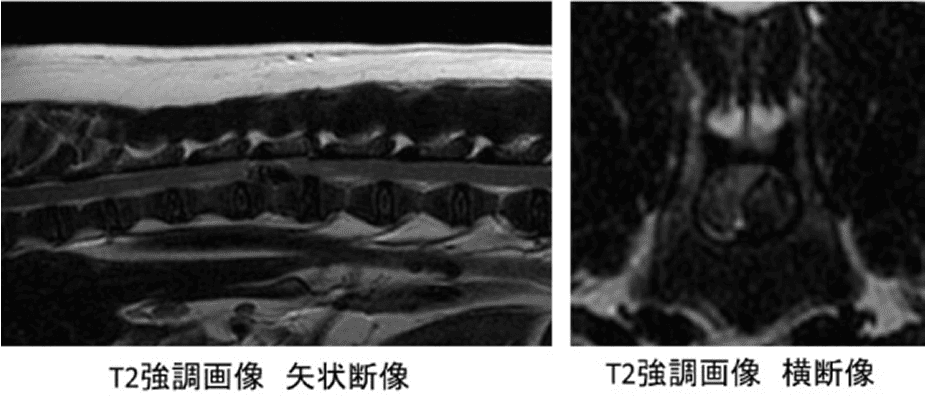

胸腰部椎間板ヘルニア

画像診断科では、おもにCT(コンピューター断層)やMRI(核磁気共鳴画像)などの断層画像を用い、様々な疾患の診断をおこなっています。

近年、CTやMRIは獣医療においても一般的な検査となっていますが、

診療科の細分化が進行していく中で、個々の獣医師が断層診断に精通し、病態を解明していくことは困難です。

そこで断層診断の専門家集団として画像診断科は、他施設様や他の診療科から依頼を受け、画像の撮影から読影、病態の分析・推論までを一括して執り行っております。